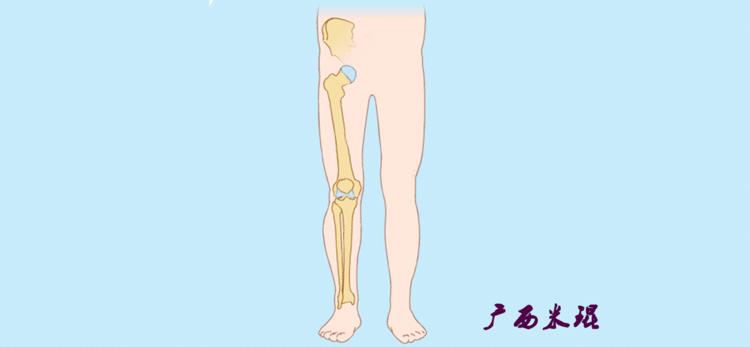

(3)垂直轴

也就是下肢的负重轴,它是身体的纵轴线,与地面垂直,由于双髋比双踝的距离宽,所以垂直轴与下肢力线(机械轴)存在3°的外翻。

开始接触时可能我们对这些轴有点混乱,通过下面的这张图片就能清楚的了解下肢几个轴之间的关系。

最常见的下肢畸形发生于冠状面,即膝内外翻畸形,冠状面的对线异常通过应用“对线异常检验”进行分析,机械轴的偏移(MAD)表现为对线异常。

膝内翻是指下肢力线通过膝关节中心点内侧,距中点2mm以上,偏内超过15mm为显著膝内翻。膝外翻是指下肢力线通过膝关节中心点外侧,距中点2mm以上,偏外超过10mm为显著膝外翻。